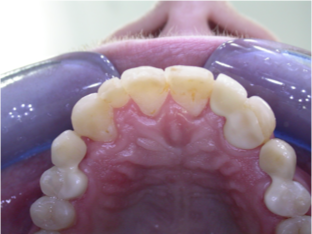

<p>identify the pontic and bridge in this image&nbsp;</p>

identify the pontic and bridge in this image

• UL2 = pontic (fake tooth)

• fixed bridges from premolars